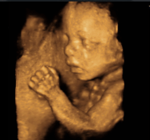

3D/4D HD Live, jetzt bereits auch in der Frühschwangerschaft!

Die Untersuchungen werden mit dem modernsten High-end Ultraschallgerät der Firma GE Healthcare, dem  Voluson E8, durchgeführt.

Die Untersuchungen werden mit dem modernsten High-end Ultraschallgerät, dem

Voluson E8 der Firma GE Healthcare, durchgeführt.

Es liefert bahnbrechende Diagnose-Tools für frühere Diagnosen.

Die revolutionäre, neue 4D Transvaginalsonde hilft fetale Fehlbildungen früher als je zuvor erkennen zu können und bietet eine verbesserte Diagnosesicherheit bei komplexen, gynäkologischen Untersuchungen.

In der Schwangerschaft ist somit eine brilliante Bilddarstellung von Anfang an möglich.

Zusätzlich zur Darstellung im Standbild, besteht die Möglichkeit Ihr Baby im Video festzuhalten.